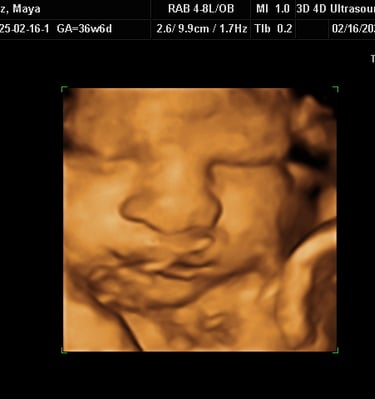

Our Gallery

Explore beautiful moments captured during our 3D and 4D sessions.